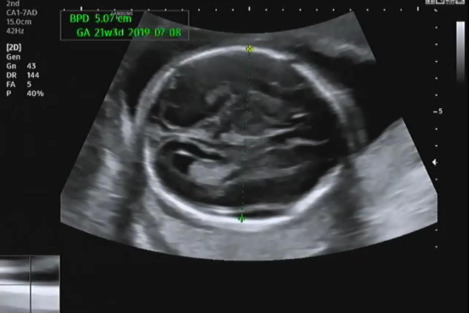

그다음 태아의 머리 둘레를 측정하고 21주 차에 맞게 뇌가 주수에 알맞게 발달하였는지, 물혹 등의 여부나 기형이 있는지 확인을 한다.